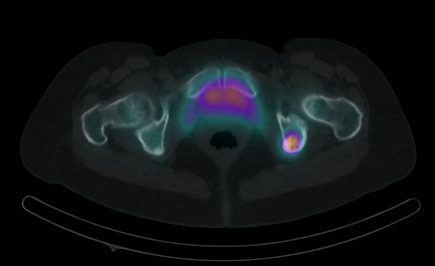

Hybridbildgebung

- Beide Fächer sind gut auf Ihrem Gebiet und blind dem jeweils anderen.

- Hybridbildgebung löst dieses Problem.

- In einem Gerät (z.B. PET/CT, SPECT/CT oder sogar PET/MRT)

- Darstellung von Funktion und Aussehen.

Vorteil: Verbesserung der diagnostischen Genauigkeit, oft insgesamt Senkung der Strahlenbelastung.